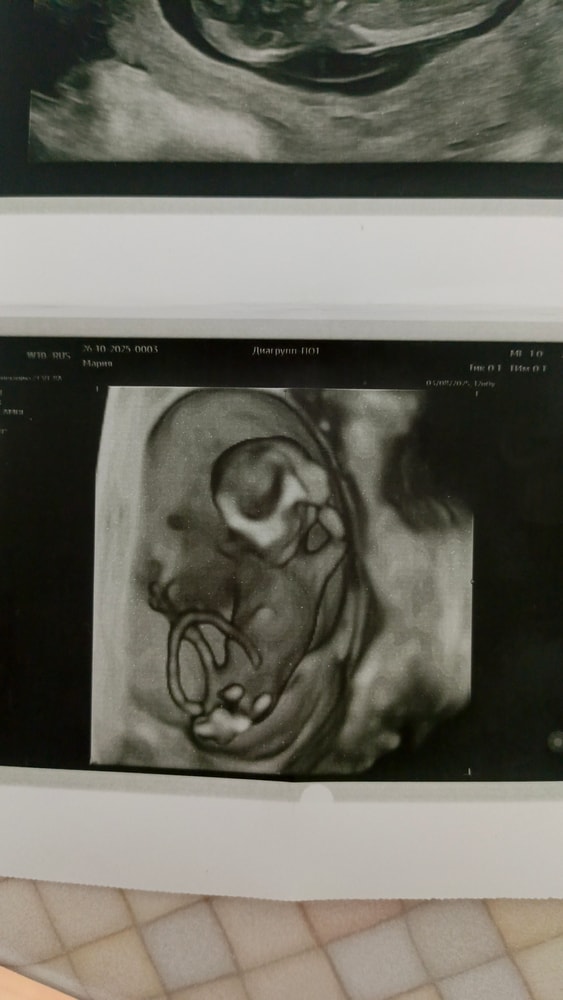

На кого похож?

Видно тут или нет ? Посередине это что на первом ?